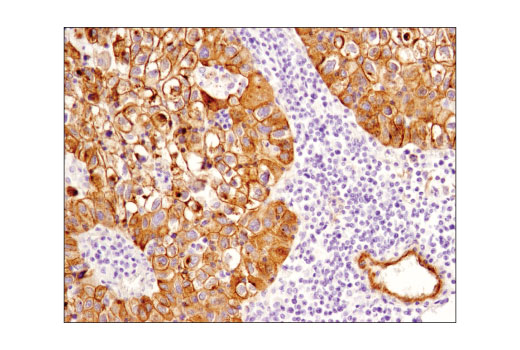

Immunohistochemical analysis of paraffin-embedded HepG2 (positive, left) and Jurkat (negative, right) cell pellets using Jagged1 (D4Y1R) XP® Rabbit mAb.

Immunohistochemistry Image 1: Jagged1 (D4Y1R) Rabbit Monoclonal Antibody